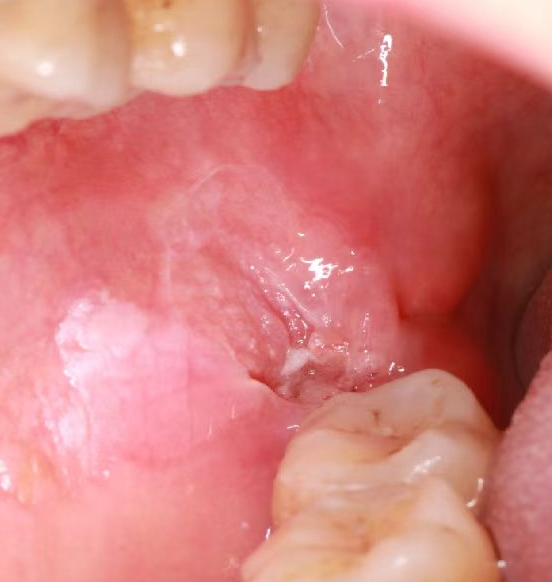

患者因右颊部肿物前往阆中市人民医院口腔科就诊,经病理检查,确诊为颊黏膜鳞状细胞癌。面对这一复杂病例,口腔科迅速联合影像科、麻醉科、病理科等多学科专家开展术前讨论,为患者量身定制了个性化手术方案。

术前口内照片